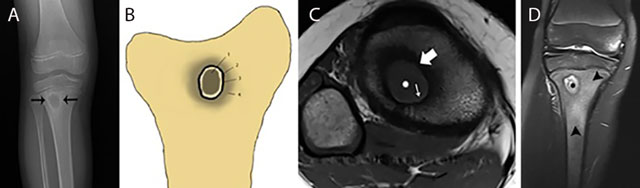

Typical Brodie abscess in subacute osteomyelitis of the tibia. Plain radiograph (a) Schematic drawing (b) Axial T1–WI (c) and coronal Fat–Sat T2–WI (d) Plain radiograph (a) shows a focal area of metaphyseal osteolysis with a peripheral rim of reactive sclerosis (black arrows). (b) shows a the different layers of Brodie abscess on T1–WI with a the pathognomonic penumbra sign on axial T1–WI (c) and a pus-filled collection on coronal Fat–Sat T2–WI (d). Central pus of intermediate to low SI on T1–WI (white asterisks on c) and high SI on T2–WI (black asterisks on d). Internal abscess wall consisting of granulation tissue of high SI on T1–WI (penumbra sign) (white small arrow on c) and intermediate SI on T2–WI. External ring of reactional sclerosis of low SI on both T1–WI (white large arrow on c) and T2–WI. Peripheral bone marrow edema of intermediate to low SI on T1–WI and high SI on T2–WI (black arrowheads on d).

Subacute osteomyelitis is characterized by the presence of Brodie’s abscess at the metaphysis. It typically presents as an oval radiolucent lesion with peripheral sclerosis within the metaphysis of the long bones on plain radiography (Figure 10). The shape of a Brodie’s abscess along the longitudinal axis may be explained by effect of gravity. More rarely, Brodie’s abscess may be located in the short and flat bones as well. The presentation of a Brodie’s abscess on MRI (Figure 10) is characterized by the penumbra sign consisting of a subtle peripheral rim of high signal on T1–WI around the pus collection in the bone. The high SI is probably due to granulation tissue in the abscess wall with lipid-laden macrophages (Figure 10) [10]. After administration of intravenous gadolinium contrast, this thin vascularized rim enhances [1112].